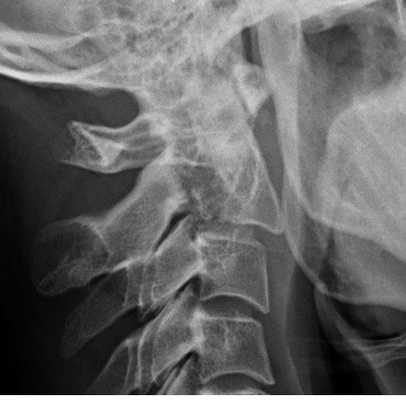

Рисунок 1 : Передний подвывих C4 по сравнению с C5 связан с увеличением зазора / дистракции фасеточного сустава. Вероятно, это связано с механизмом гиперфлексии.

Латеральная проекция

Латеральная проекция шейного отдела позвоночника представляет собой наиболее важное рентгенологическое исследование повреждения шейного отдела позвоночника. Перед выполнением любых других снимков необходимо получить и изучить боковую рентгенограмму. Необходимо визуализировать все 7 шейных позвонков и соединение C7-T1, поскольку шейно-грудной отдел является частым местом травматических повреждений. Адекватная визуализация C7-T1 может быть ограничена мягкими тканями в области плеча и может быть улучшена либо за счет вытяжения за руки (при отсутствии травмы руки), либо за счет позы пловца (одна рука вытянута над головой). Иногда повторная боковая рентгенограмма с удаленным шейным воротником может прояснить подозрительные поражения.

Первое наблюдение, которое необходимо сделать на боковой рентгенограмме - это выравнивание тел позвонков. Необходимо выровнять передний и задний края тел позвонков, спиноламинарную линию и кончики остистых отростков. Любой «шаг» в выравнивании считается ненормальным и должен рассматриваться как свидетельство повреждения связки или скрытого перелома; таким образом, иммобилизация шейного отдела позвоночника должна сохраняться до постановки окончательного диагноза.